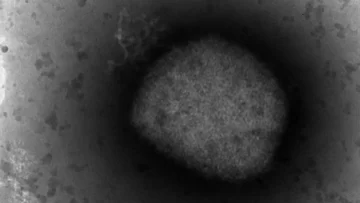

Una mujer ha resultado infectada por la viruela del mono en la Comunidad de Madrid y está directamente relacionada con la cadena de transmisión de relaciones entre hombres, según fuentes de la Consejería de Sanidad.

Los casos certificados o sospechosos de viruela del mono han aumentado en España, hasta superar los 80 verificados y más de 150 pendientes de confirmación, distribuidos en nueve comunidades autónomas, después de que Castilla y León descartara su único posible contagio y Cataluña se haya sumado con cuatro infectados.